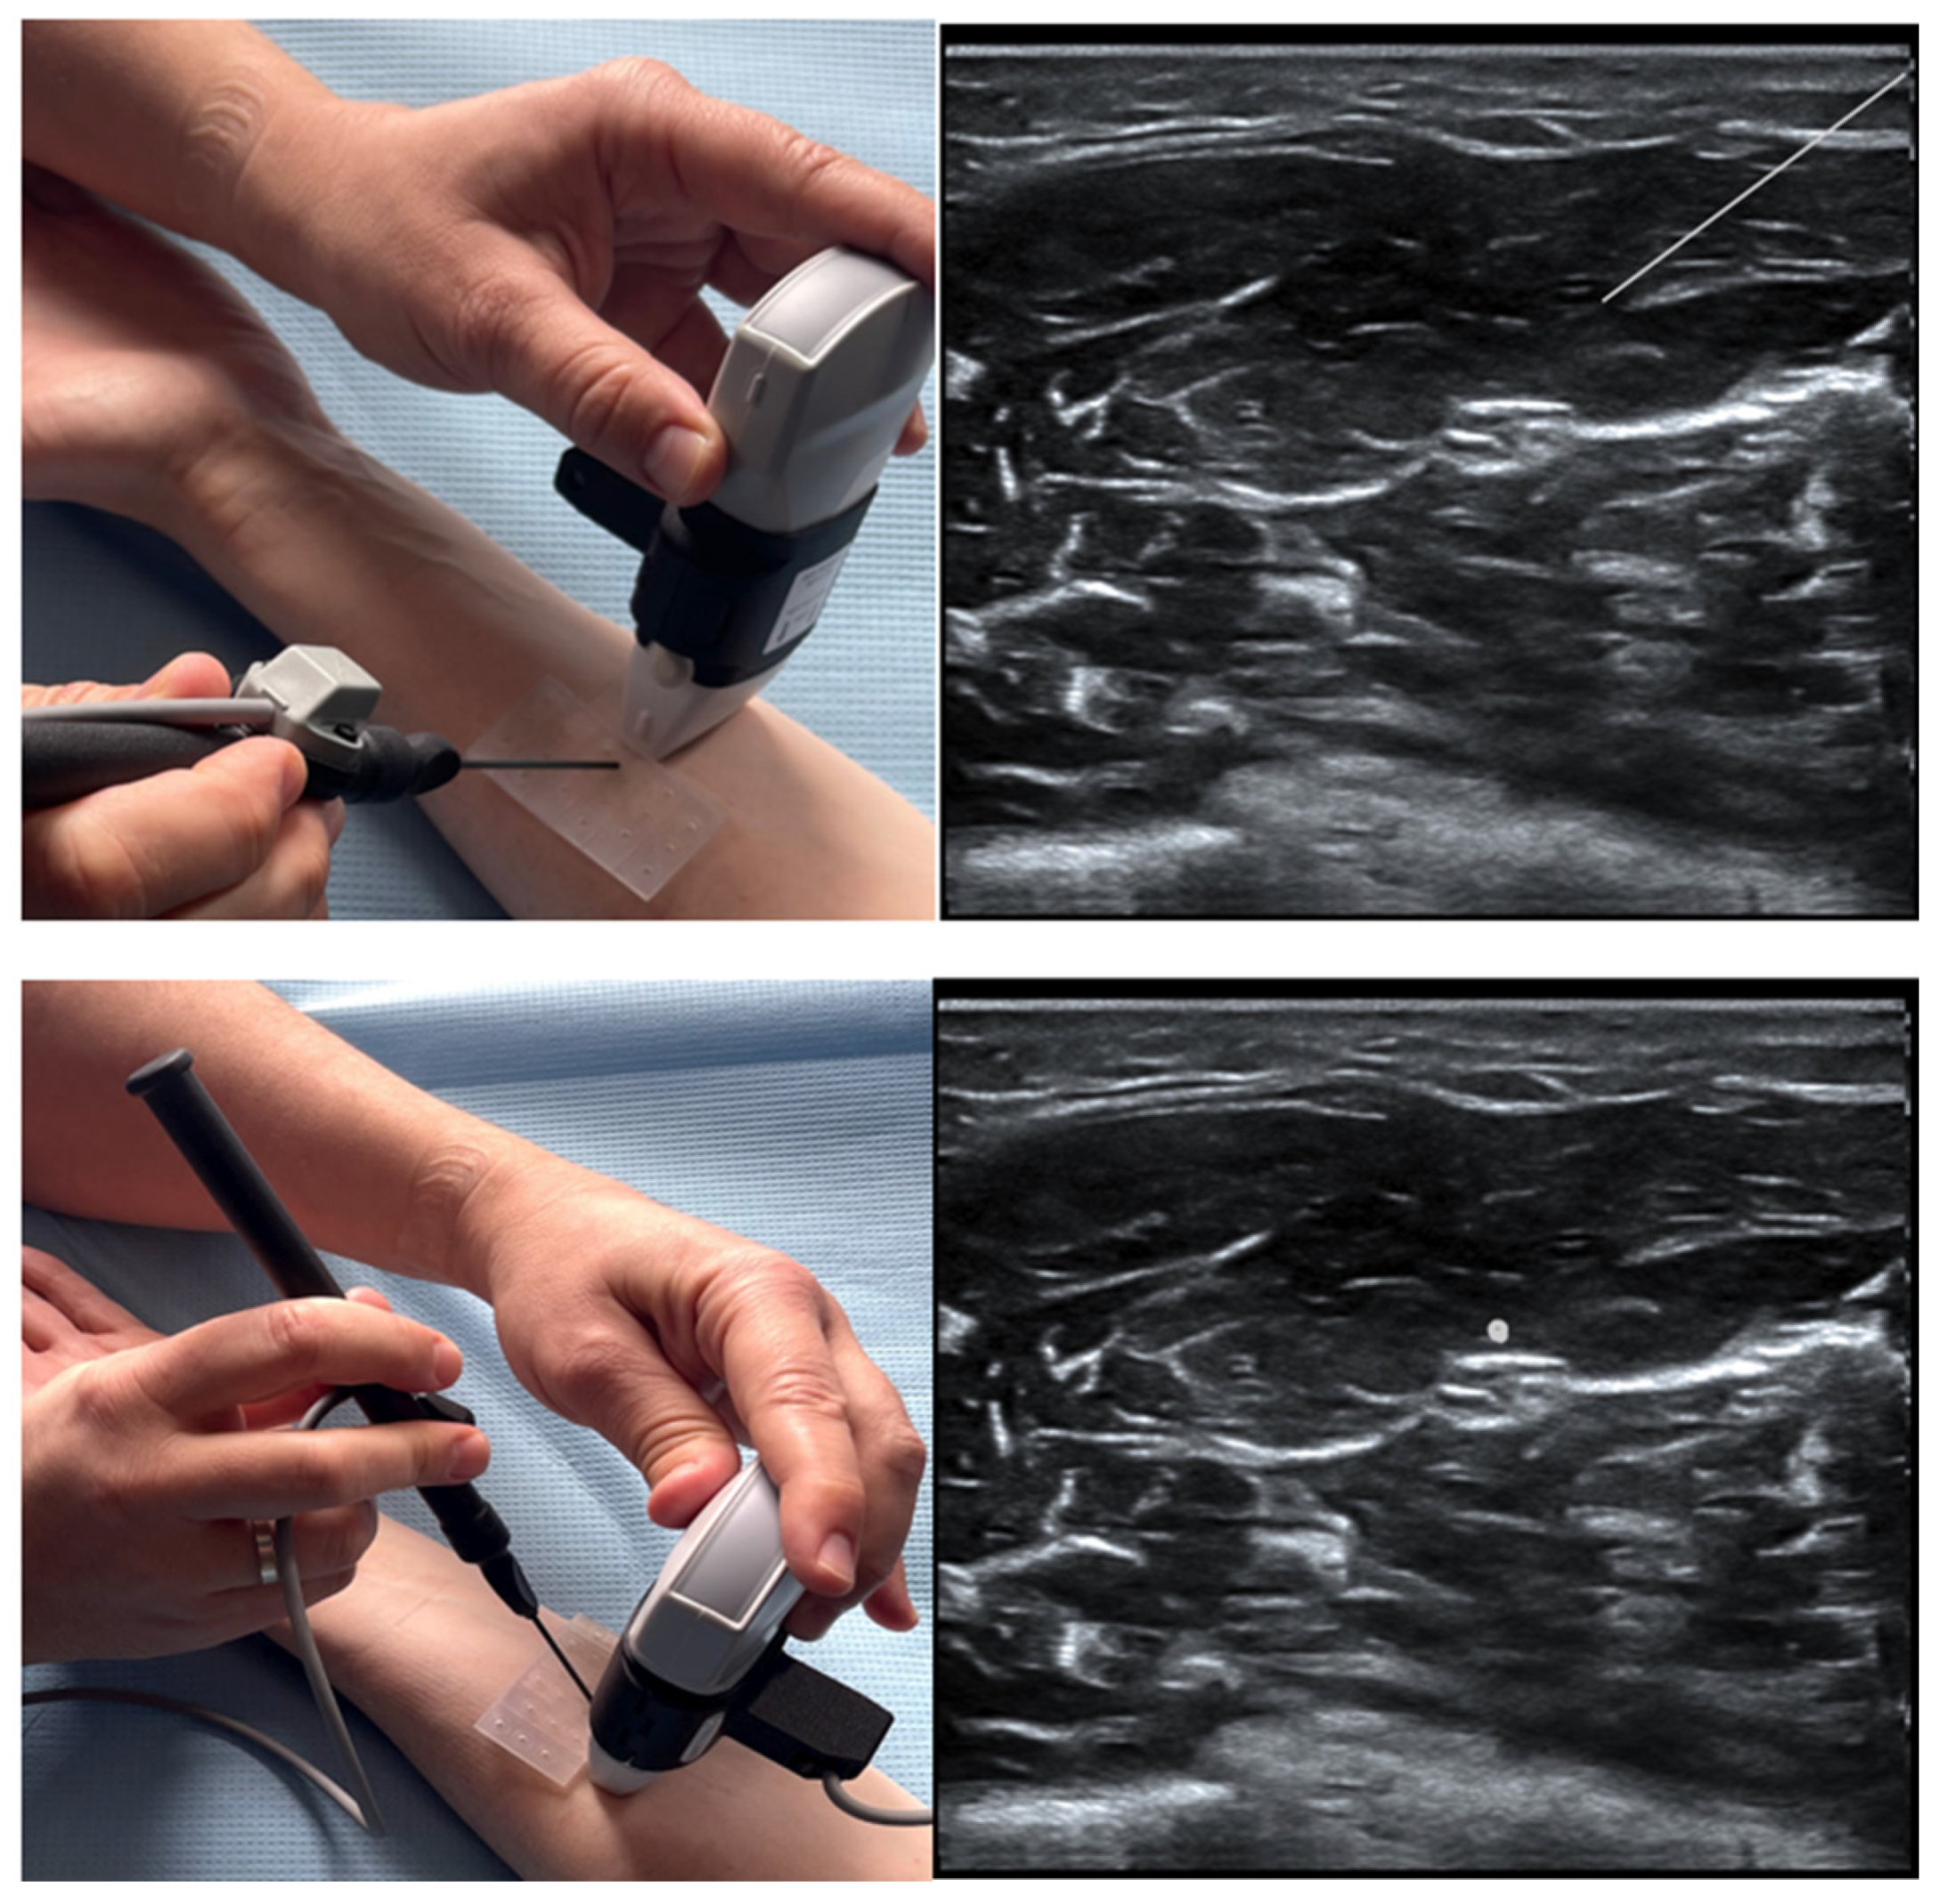

| Scanning with AL Assistive Device | Scanning without AL Assistive Device | Alpha (p-Value) | |

|---|---|---|---|

| Correct block view, n (%) | 56/62 (90.3) | 47/62 (75.1) | 0.031 |

| Correct structure identification, n (%) | 188/212 (88.8) | 161/208 (77.4) | 0.002 |

| Median confidence (IQR) | 8 (6–10) | 7 (6–10) | 0.155 |

| Median global rating score (IQR) | 7 (6–9) | 7 (4–9) | 0.225 |

| Mean scan time (SD), s | 75.9 (69.6) | 74.5 (65.6) | 0.881 |